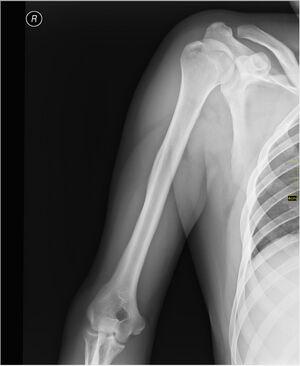

Плечо́ (лат. brachium) — отдел верхней конечности. Оно располагается между плечевым поясом и предплечьем, и соединяется с ними посредством плечевого сустава и локтевого соответственно.

Скелет[править | править код]

Каркасом плеча служит плечевая кость.

При травмах плеча возможно повреждение нервов и сосудов, а также переломы плечевой кости, наиболее частой локализацией которых является шейка плечевой кости[1].